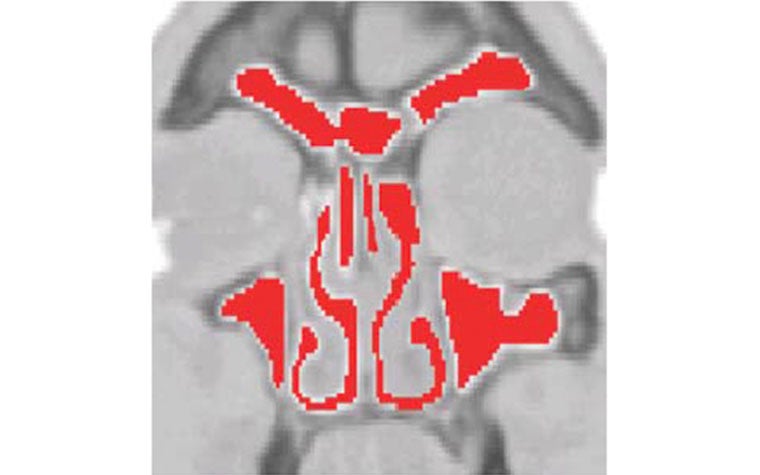

The construction of a surface mesh, based on CT data of the inner nasal cavity, is done in two main steps. First, the region of interest is segmented and represented as an STL surface mesh. Then, the unresolved fine structures, which are crucial for the flow characteristics, are reconstructed. For the first step, Dr. Krause applied seeded and dynamic region growing segmentation schemes. By doing so, he was able to identify the region of interest according to a defined color level or a special change.

Mimics Core proved ideal for accomplishing this step, and to a large extent, it automated the process. The second step, the reconstruction of unresolved structures like small air cavities, paranasal sinuses, and thin passages and tissues, was performed with the help of physicians, 3D visualization techniques, and 3-matic. For this study, the small tissue separating two passages could not be reconstructed completely. However, some captured parts of the tissue formed a needle structure in the segmented surface representation, so the problem could be solved using tools in 3-matic.